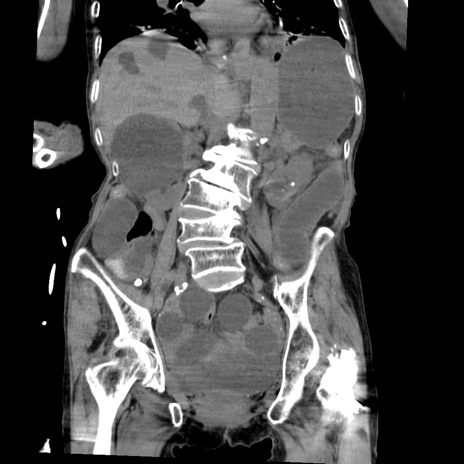

症例27(冠状断像)

【症例】80歳代女性

【主訴】嘔吐、腹痛

【現病歴】数時間前より嘔吐あり。心窩部痛出現し、徐々に右下腹痛あり。その後も数回嘔吐あり救急搬送となる。

【既往歴】左大腿骨頚部骨折手術

【身体所見】腹部は膨隆しているが軟らかく圧痛なし。腸雑音はやや亢進。

【データ】WBC 12000、CRP 19.05